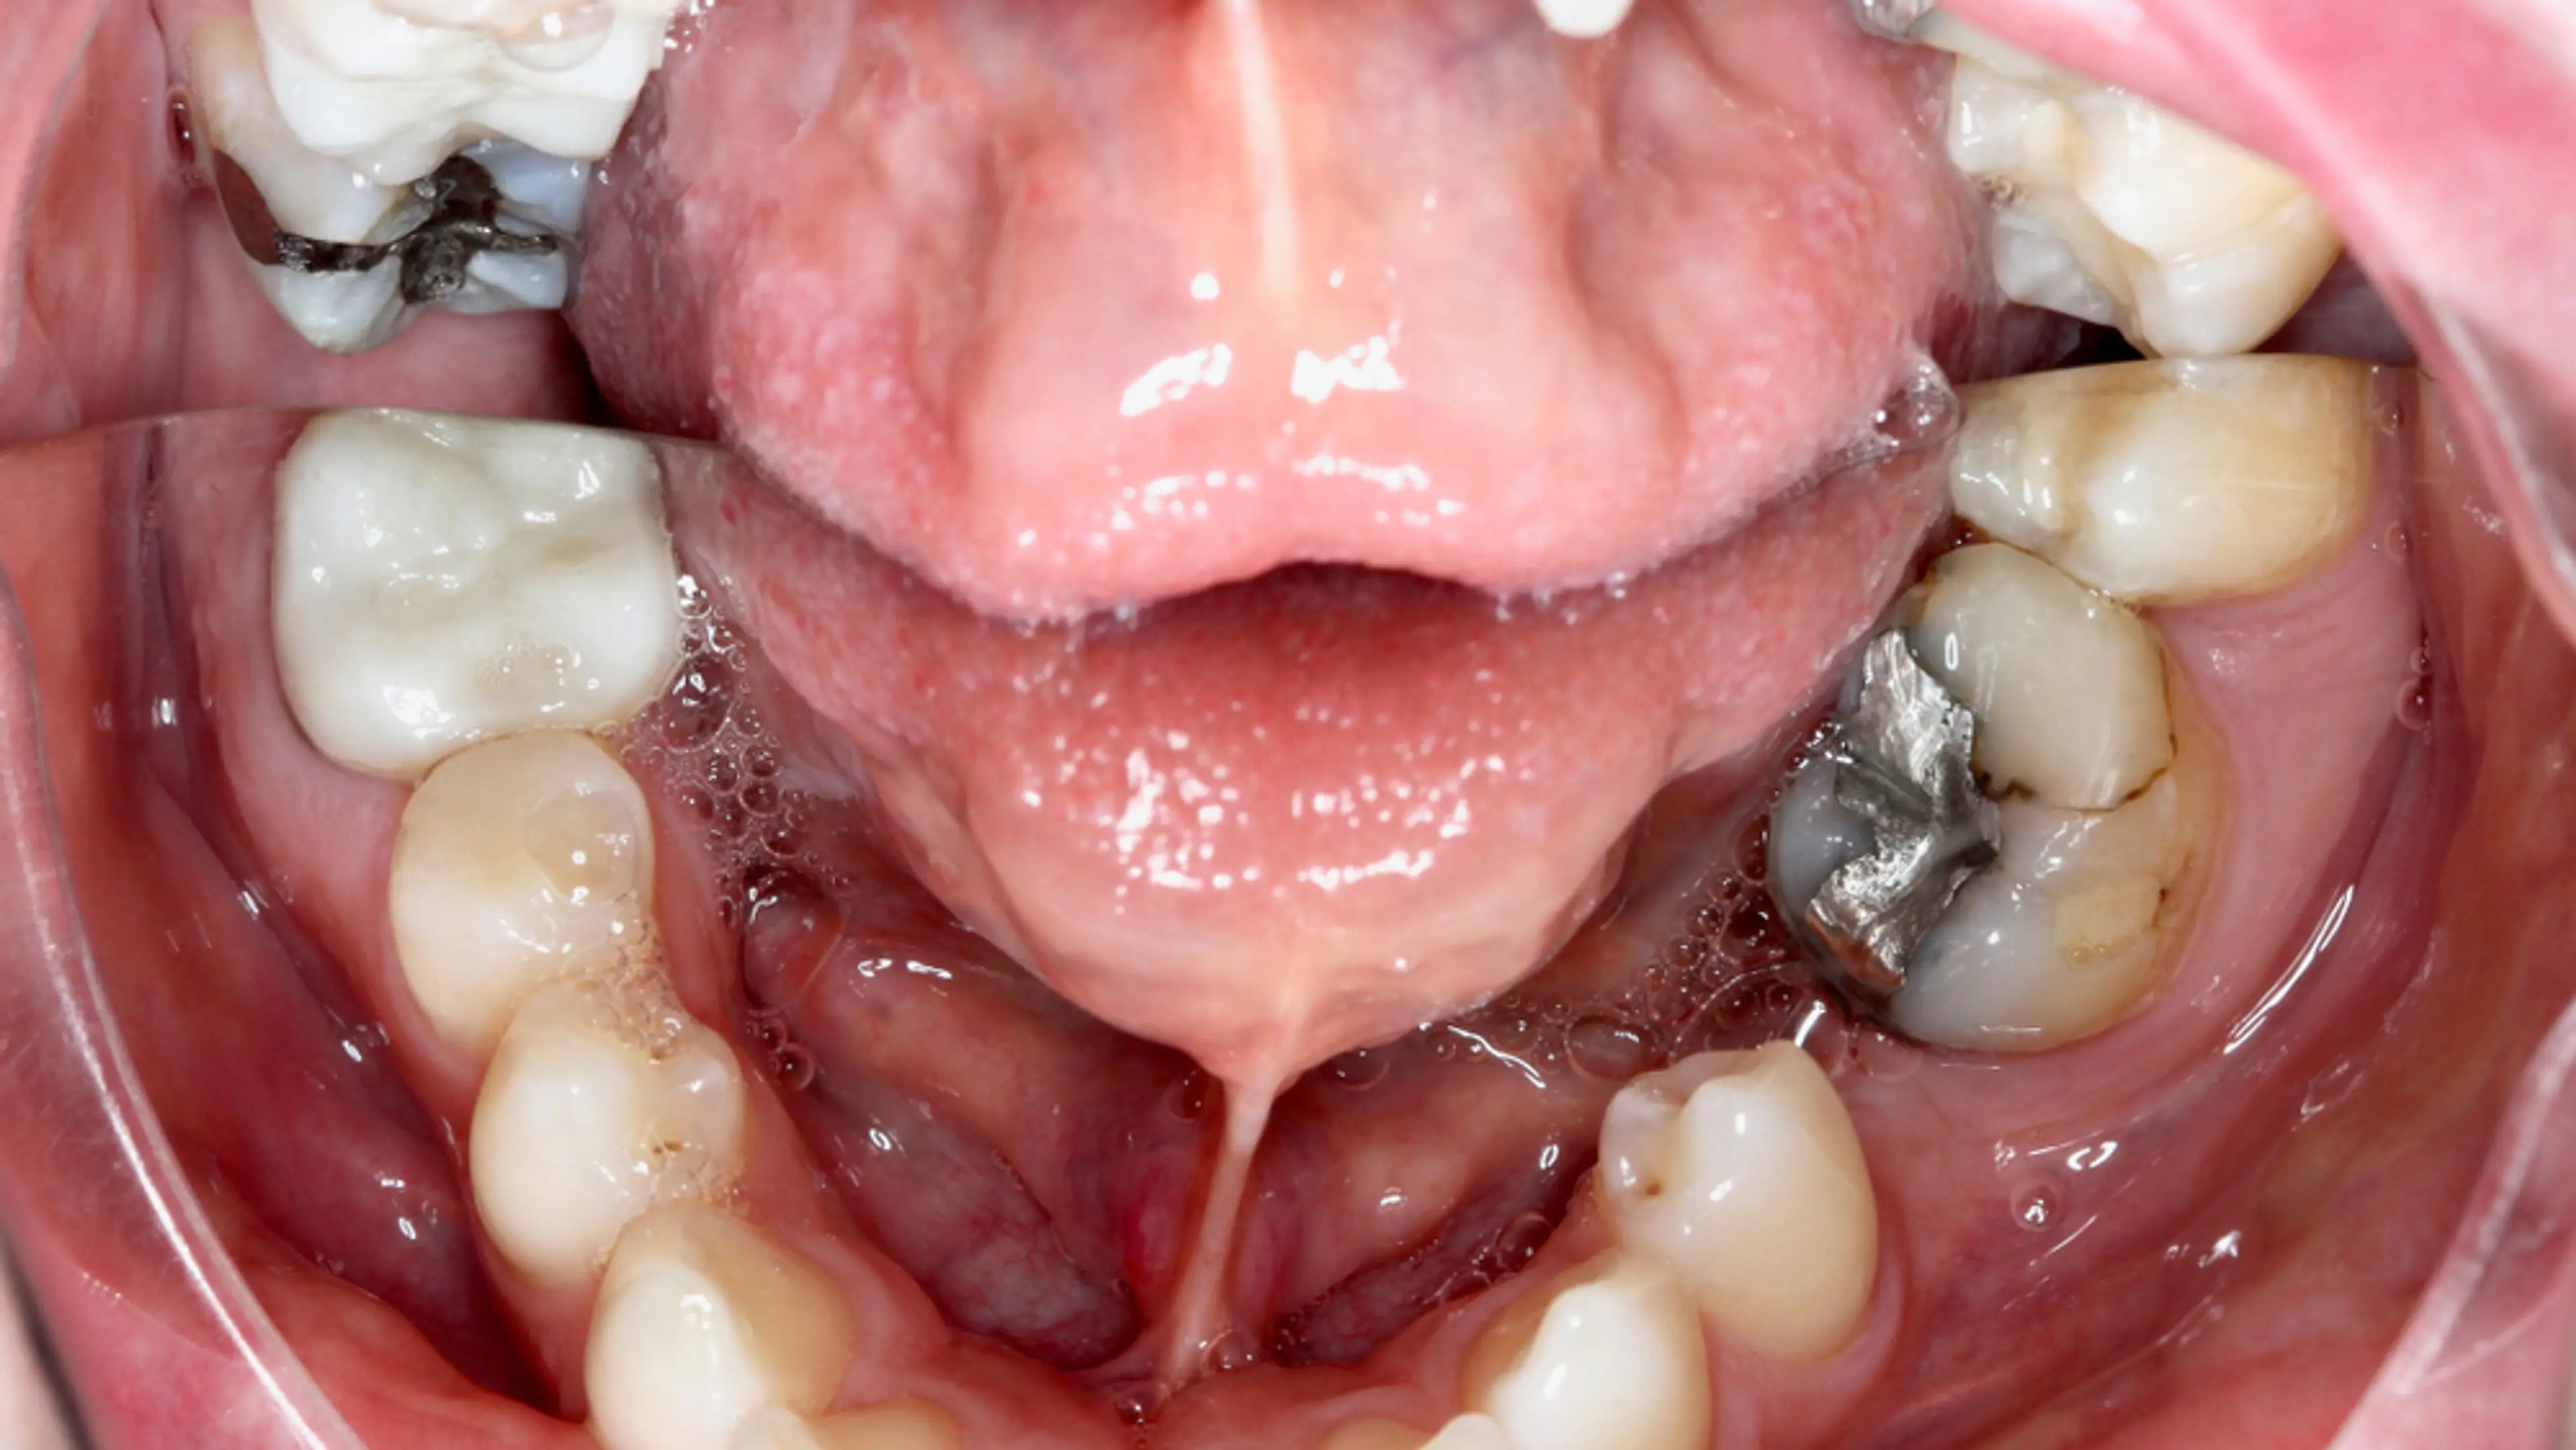

补牙是用修复材料来填补牙齿因蛀牙或外伤造成的轻度到中度损坏。补牙的目的是封闭牙洞,保护牙齿内部结构。补牙材料有很多种,比如复合树脂、银汞合金、瓷、甚至黄金,但每种材料都有使用寿命。

所谓补牙“失败”,就是补牙材料无法继续发挥保护作用,可能因为出现裂缝、渗漏、材料老化或补牙周围再次蛀牙。这样一来,牙齿的保护屏障被破坏,细菌、食物残渣和咬合压力都可能对牙齿造成进一步伤害。

• 材料本身的局限性:银汞合金填充物在冷热变化时会膨胀或收缩,可能导致周围牙釉质出现裂纹。树脂复合材料虽然美观,但在某些情况下磨损速度较快。

4. 补牙周围出现黑斑或变色

4.-dark-stains-or-discoloration-around-the-filling

补牙边缘出现黑影或色斑,可能说明有微渗漏或牙齿再次蛀坏。尤其是前牙出现这种情况,会影响美观。

在我们位于江南的诊所,许多患者都希望补牙后效果隐形且持久。因此,我们常常在显微镜辅助下,选用高品质的复合树脂和陶瓷材料,确保补牙精准贴合。我们也会定期将老旧的银汞合金(俗称“黑色补牙”)更换为更安全、外观自然、符合现代美学的生物相容性材料。